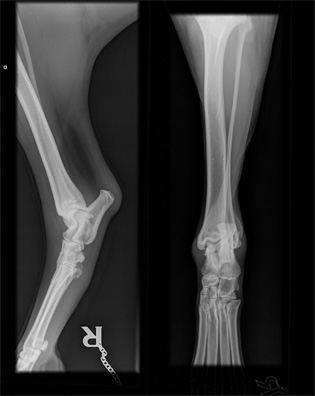

Norpan kinnerten ja kyynärten röntgenkuvat

Norpan jalkavaivoista tai yleensä OCD:sta kiinnostuneet voivat vilkaista alla olevia kuvia. Kuvat on otettu ajalta ennen kinnerten tähystystä ja ne saa suuremmaksi klikkaamalla. Lisäsin linkkien takaa löytyviin kinnerkuviin muutamia huomioita, jotka jäivät Esa Eskeliseltä ja Kai Skutnabbilta haetuista lausunnoista mieleen. En osaa itse tulkita röntgenkuvia, joten toivottavasti muistini ei reistaillut noita yksityiskohtia merkkaillessa. Kyynärkuvista jätin huomiot pois, koska en osaa osoittaa vasemmasta kyynärästä riittävän tarkasti sitä kohtaa, jossa Skutin mukaan on vähäisiä reaktioita havaittavissa. Eskelinen suositteli lausunnossaan myös kyynärnivelten tähystämistä, mutta Skutin mukaan oikea kyynärnivel on puhdas eivätkä vasemmankaan reaktiot viittaa OCD:hen.

Kinnernivelet